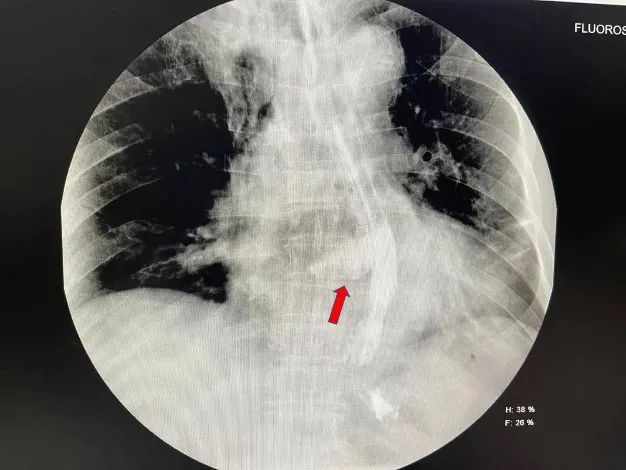

刘大爷今年已经73岁高龄,1年前因脑中风,一侧身体活动不便,平时需要轮椅辅助活动。一年一度的端午节,家中裹了不少美味粽子。节前一天(6月13日)中午,刘大爷禁不住尝了一个,谁知两口下去,胸背部开始剧烈疼痛。儿子连忙带他到当地医院就诊。心电图检查排除冠心病,心脏彩超未见明显异常,仅胸部CT提示少量纵膈积气。然而,在就诊过程中,刘大爷逐渐呼吸不畅,被紧急送进了ICU病房观察。由于担心患者晚间病情恶化,医生建议家人立即送患者到上级医院就诊。当晚11点,刘大爷便在家人陪同下转入珠江医院重症医学科。考虑到患者纵膈气肿原因不明,值班医生立即通知胸外科会诊,并在入院时加急完成胸部CT检查。在询问病史及阅读患者CT片后,一个细节让胸外科副主任医师李辉警觉起来——患者食管下段右侧壁隐约有一条线样的空腔通向右侧胸腔,右侧胸腔有少量的积液及肺不张。“单纯的纵膈气肿很少这么快引起胸腔积液和肺不张,难不成是吞咽粽子时造成的食管破裂?不行,要马上进行食管造影!”李辉当机立断。检查结果中,只见患者食管下段造影剂自食管右侧壁一条大约3cm长的破口渗漏至右侧纵膈,果然是食管破裂。

食管造影提示食管破裂“